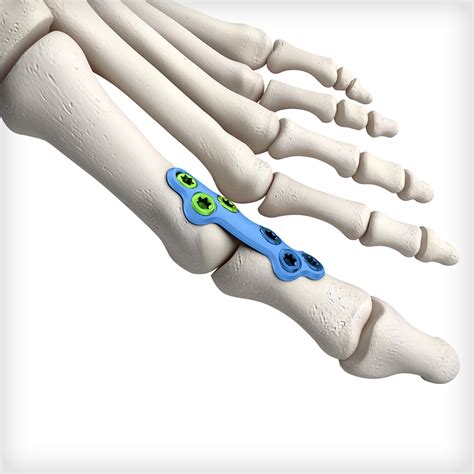

Ankle Fusion Procedures work by removing the damaged cartilage from the joint surfaces of the talus (the top bone of the foot) and the tibia (the shin bone). Once the cartilage is removed, the surgeon uses metal hardware, such as plates, screws, or rods, to hold these two bones together in a fixed position. Over the course of several months, the body naturally heals by bridging these bones with new bone tissue, creating a single, solid bone structure. The primary goal is to eliminate pain by preventing the grinding of bone-on-bone that occurs in advanced arthritis.